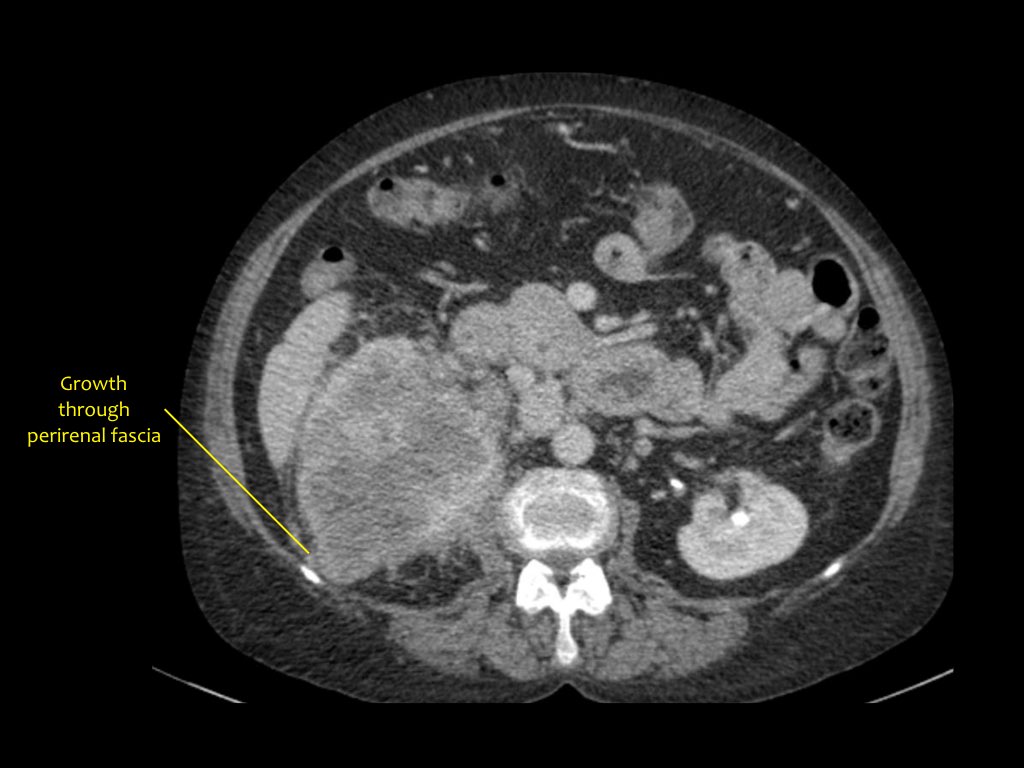

Phân giai đoạn RCC

RCC có thể xâm lấn mỡ quanh thận vượt qua cân thận và có thể lan vào tĩnh mạch thận, tĩnh mạch chủ dưới (IVC) hoặc tuyến thượng thận cùng bên.

Đối với phẫu thuật viên, điều quan trọng là cần biết có huyết khối u trong IVC hay không và liệu huyết khối có lan vào lồng ngực trên cơ hoành hay không (cần có phẫu thuật viên lồng ngực trong ca mổ).